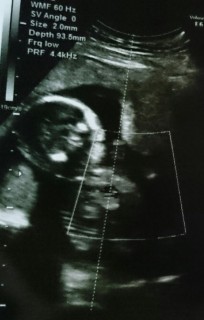

風邪をひき、体がすごく楽になってしまったこと、何となく感じていた胎動を感じられなくなってしまったことが心配で病院に行きました。 私の心配をよそに赤ちゃんは指を一生懸命閉じたり開いたりしていて、体も丸くなっていて愛しさが増しました。 エコー写真も何だか笑っているみたいに見えます。風邪で辛かったけれど、元気な我が子の姿に励まされました☆